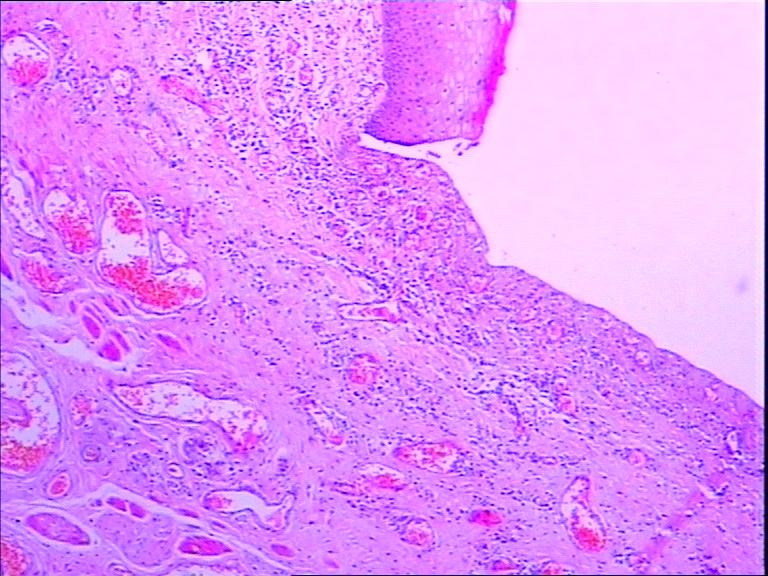

包皮溃疡该怎么办?包皮溃疡大家应该觉得很稀奇,包皮也能溃疡?这种说法了解的人几乎没有,但如果说是包皮龟头炎,我想这下大家应该就明白了,包皮溃疡是包皮龟头炎症状表现之一。所以,要对其加大重视,所以,了解包皮溃疡后要出现此症状要及早进行治疗。那么,包皮溃疡该怎么办?下面由北海泌尿专科医院专家为大家介绍一下:

1、滴虫感染:多是由于妻子存在阴道滴虫病而被传染,主要表现为龟头部起红斑丘疹、小水疱等。境界清楚、范围逐渐扩大,病人常感瘙痒,在分泌物中可找到滴虫。

2、念珠菌是一种条件致病真菌,一般念珠菌性包皮龟头炎常继发于糖尿病,老年消耗性疾病以及大量抗生素或激素治疗之后,也可为原发性,多由配偶念珠菌阴道炎传来,龟头及冠状沟可有浅红色糜烂及薄壁脓疱。

3、阿米巴原虫感染,病人会出现阴茎发炎,局部失去正常的屏障作用,继而由肠道阿米巴病传染而引起,并且局部糜烂、溃疡、组织坏死,分泌物直接涂片可找到阿米巴原虫。

4、非感染因素,男性的局部创伤、摩擦、避孕药、肥皂和清洁剂等刺激,此外,男性存在包皮过长,也会导致一些包皮垢的发生,会导致阴茎发炎,出现包皮里面有溃疡的症状。